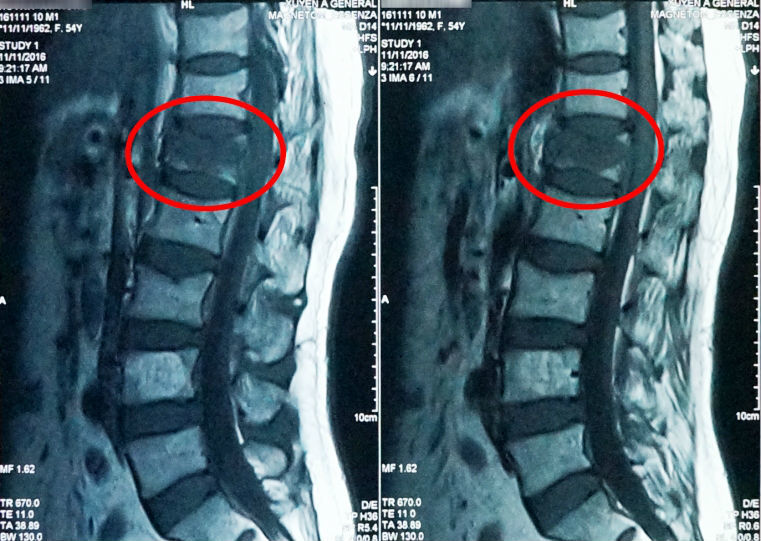

| Nữ bệnh nhân bị xẹp đốt sống sau khi bị té ngã |

Kết quả MRI 1.5 Tesla, các bác sĩ khoa Ngoại Thần Kinh nhận thấy bệnh nhân bị xẹp đốt sống L1. Ngoài ra người phụ nữ này còn bị loãng xương. Và khi té ngã thì rất dễ bị xẹp đốt sống.